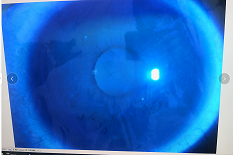

圓錐角膜要做那種治療比較好

【文章導(dǎo)讀】圓錐角膜的治療應(yīng)該依據(jù)角膜發(fā)展的時(shí)期選擇。目前圓錐角膜按照臨床癥狀大致可以分為四個(gè)時(shí)期,分別為潛伏期、初發(fā)期、完成期和瘢痕期,各個(gè)時(shí)期的主要癥狀表現(xiàn)如下: 潛伏期:

圓錐角膜的治療應(yīng)該依據(jù)角膜發(fā)展的時(shí)期選擇。目前圓錐角膜按照臨床癥狀大致可以分為四個(gè)時(shí)期,分別為潛伏期、初發(fā)期、完成期和瘢痕期,各個(gè)時(shí)期的主要癥狀表現(xiàn)如下:

潛伏期:癥狀不明顯。

初發(fā)期:開始近視,同時(shí)散光和不規(guī)則散光度數(shù)也會(huì)逐漸增加。

完成期:發(fā)展迅速,角膜明顯前突,視力銳減。

瘢痕期:角膜急性角膜水腫、混濁,消退后基質(zhì)層殘留瘢痕。

對(duì)于對(duì)于進(jìn)展非常慢,可能幾年曲率都不變化的圓錐角膜,可以觀察隨診,或者佩戴RGP矯正。如果角膜發(fā)展較快,近視散光度數(shù)增加較快,則需要通過角膜交聯(lián)來治療。

圓錐角膜的形成機(jī)制就是膠原變薄,變?nèi)酢A錐角膜患者的角膜膠原變薄了以后,彈性增加,正常的眼壓會(huì)使角膜向前膨隆。

角膜膠原交聯(lián)手術(shù)可以通過藥物,維生素B2和紫外線交聯(lián),使角膜里面的膠原纖維的硬度增加,在對(duì)抗正常眼壓情況下,對(duì)抗力增加。交聯(lián)后角膜的韌度增加,就不容易再往前繼續(xù)發(fā)展。

但如果已經(jīng)發(fā)展到圓錐后期,再去交聯(lián)就沒有意義,就只能通過角膜移植手術(shù)治療,把向前凸起的角膜給切掉,換成新的角膜。

目前圓錐角膜的治療方式主要就是配鏡矯正、角膜膠原交聯(lián)手術(shù)以及角膜移植手術(shù)這幾種。